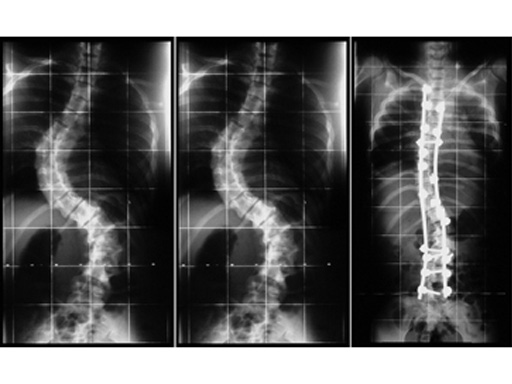

Clinical case

16-year-old woman with progressive kyphoscoliosis (scoliotic double curve: preoperative thoracic 78 and lumbar 68; postoperative 38 and 30); posterior instrumentation with pedicle screws in L1 to L5 and pedicle, lamina and transverse process hooks in T2 to T10 after anterior release.